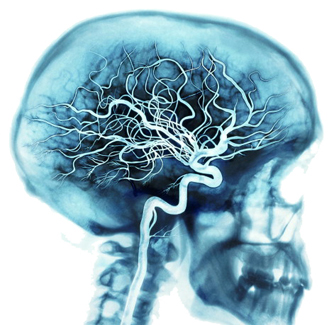

大腦的養分是由體內最龐大、最密集的血管網絡所提供。

心每跳一下,動脈就會輸送百分之 20 至 25 的血液到腦部,數千億的腦細胞平均消耗血液中約 20% 的氧氣和養分。

而當人在不斷思考及動腦筋的時候,腦部便會消耗掉血液中高達50% 的氧氣和養分。

除動脈之外,血管網絡還包括靜脈和微血管。